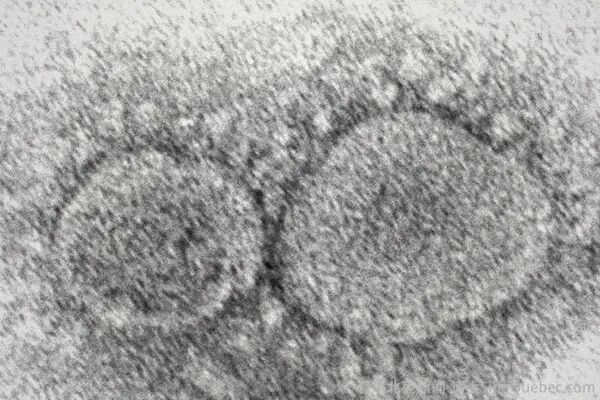

示意图:电子显微镜下的新冠病毒粒子